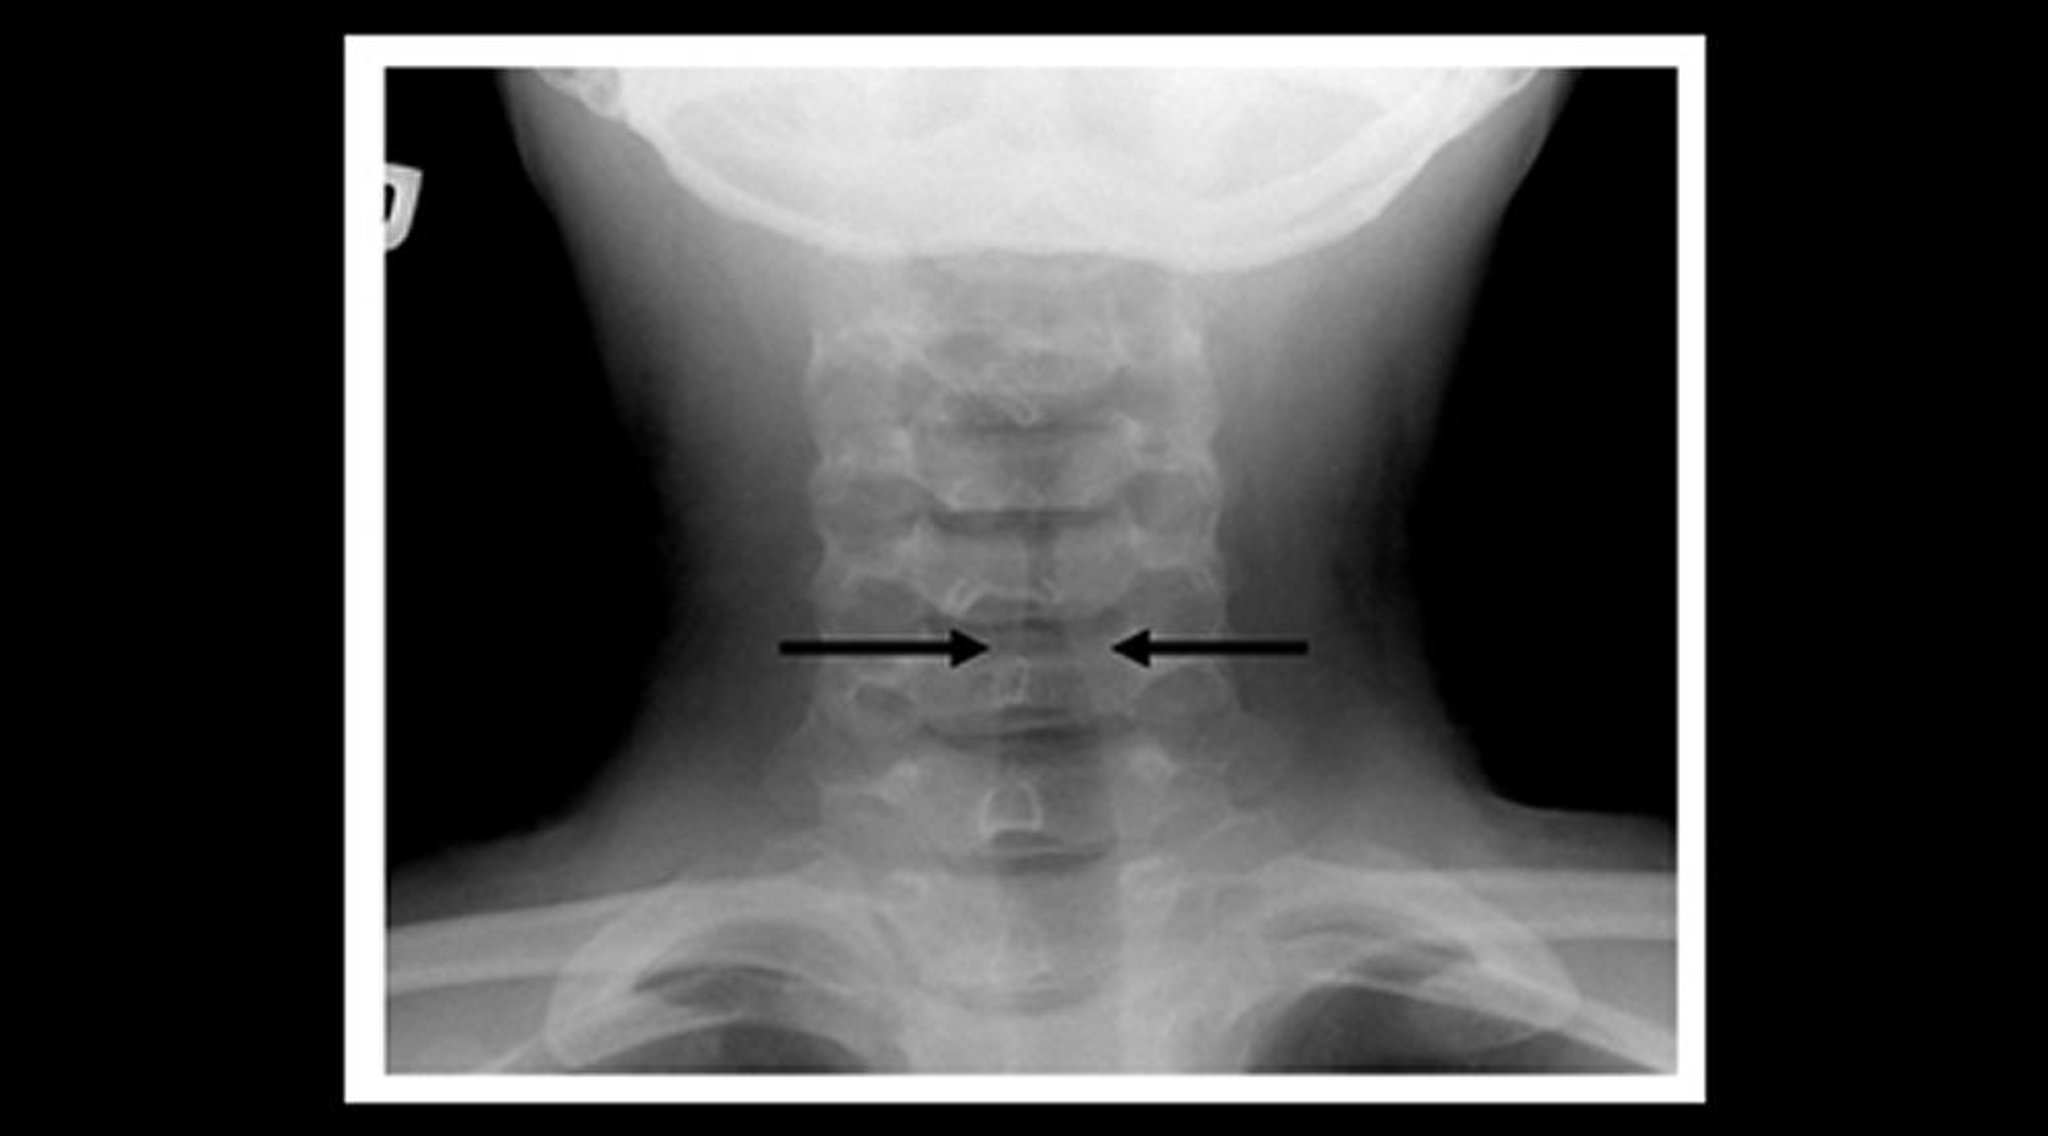

Radiografia de uma criança com crupe (plano coronal)

Radiografia de tecidos moles do pescoço de uma criança com crupe mostra estreitamento gradual da sombra de ar subglótico na traqueia (sinal de torre de igreja; setas) e dilatação dos espaços aéreos da faringe.